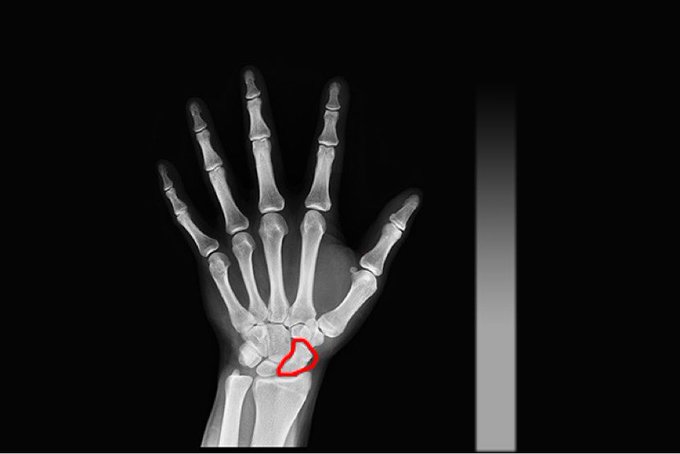

あー... 指の骨ヒビ入ってるかもしれん.. MRIとかめんどくせぇよぉ! 舟状骨折れたことある人いたらどんなんやったか教えて..